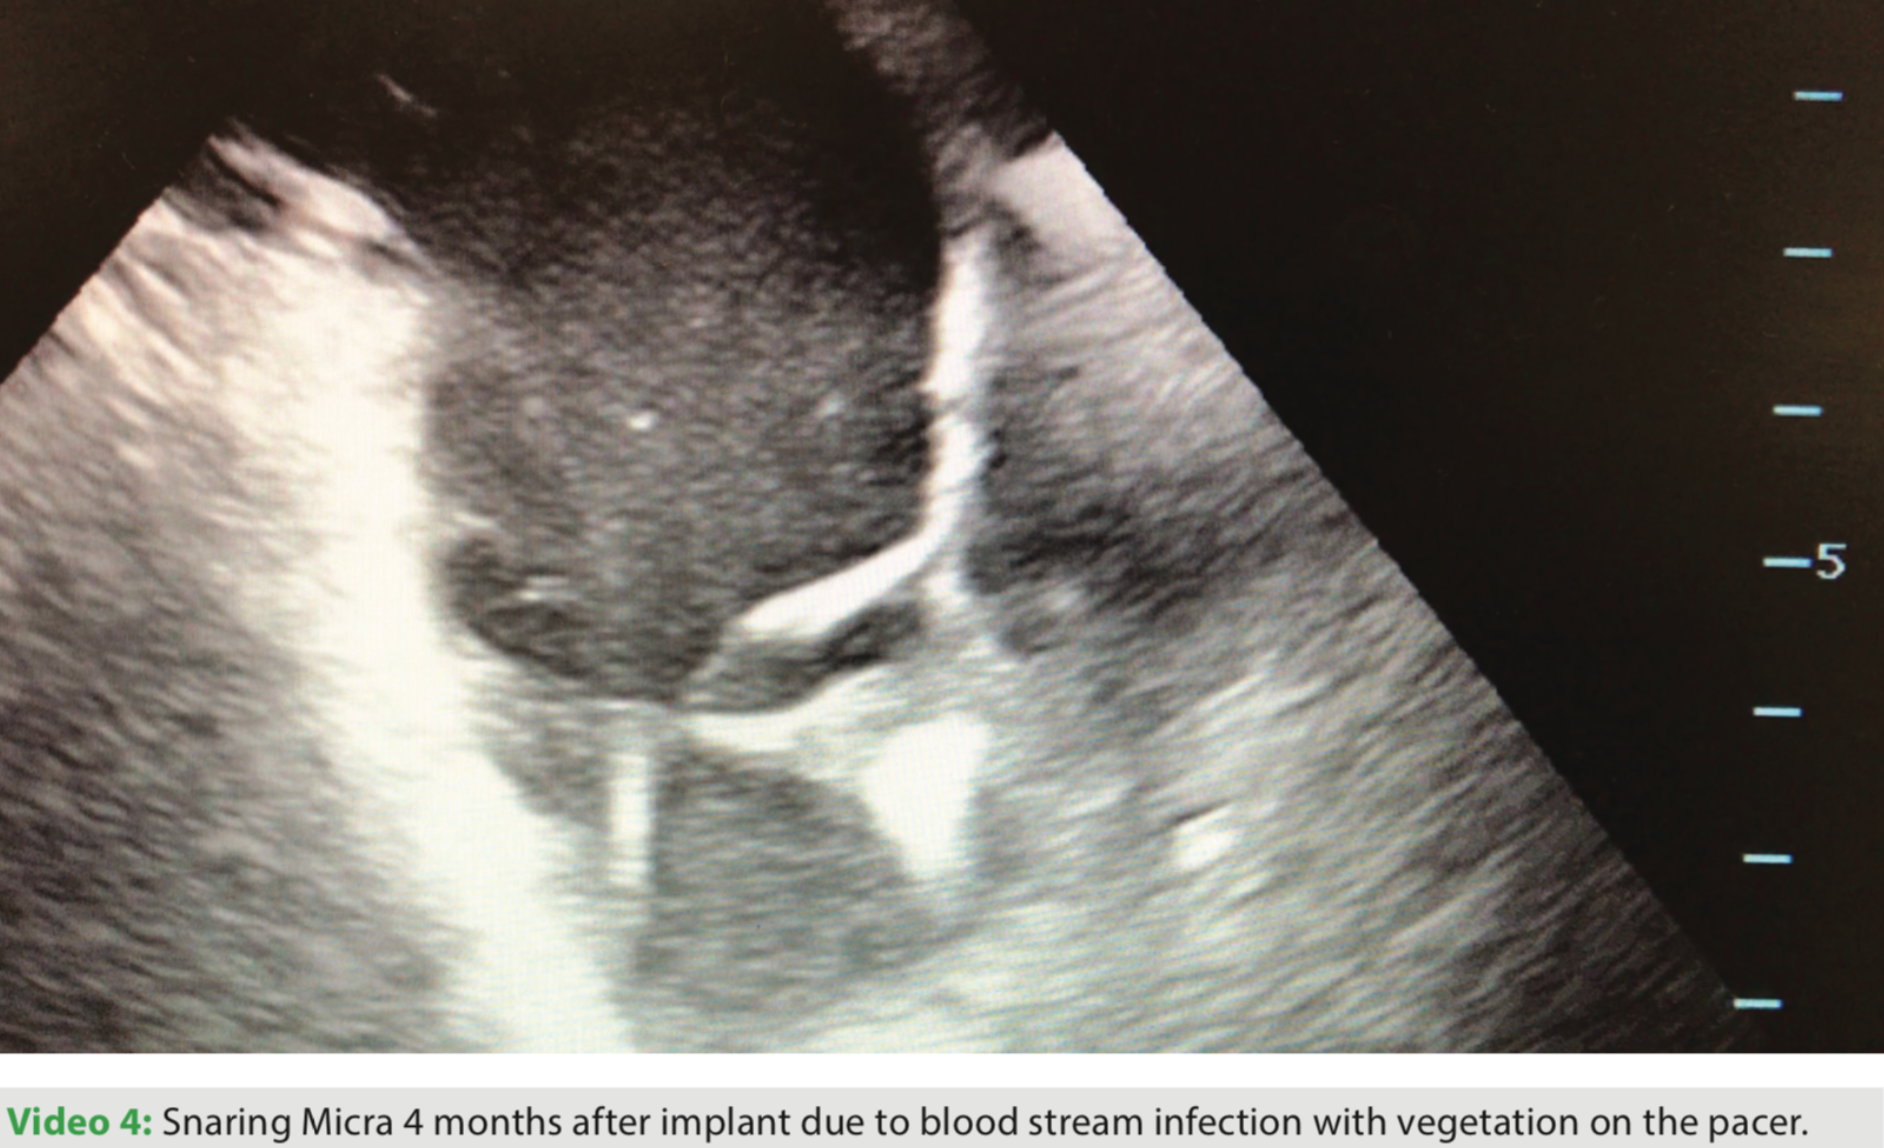

If recapture is required, it is best to do so before the tether is cut. If the device is free, a snare may be delivered through the Micra delivery catheter or through a large deflectable sheath. (Video 4)